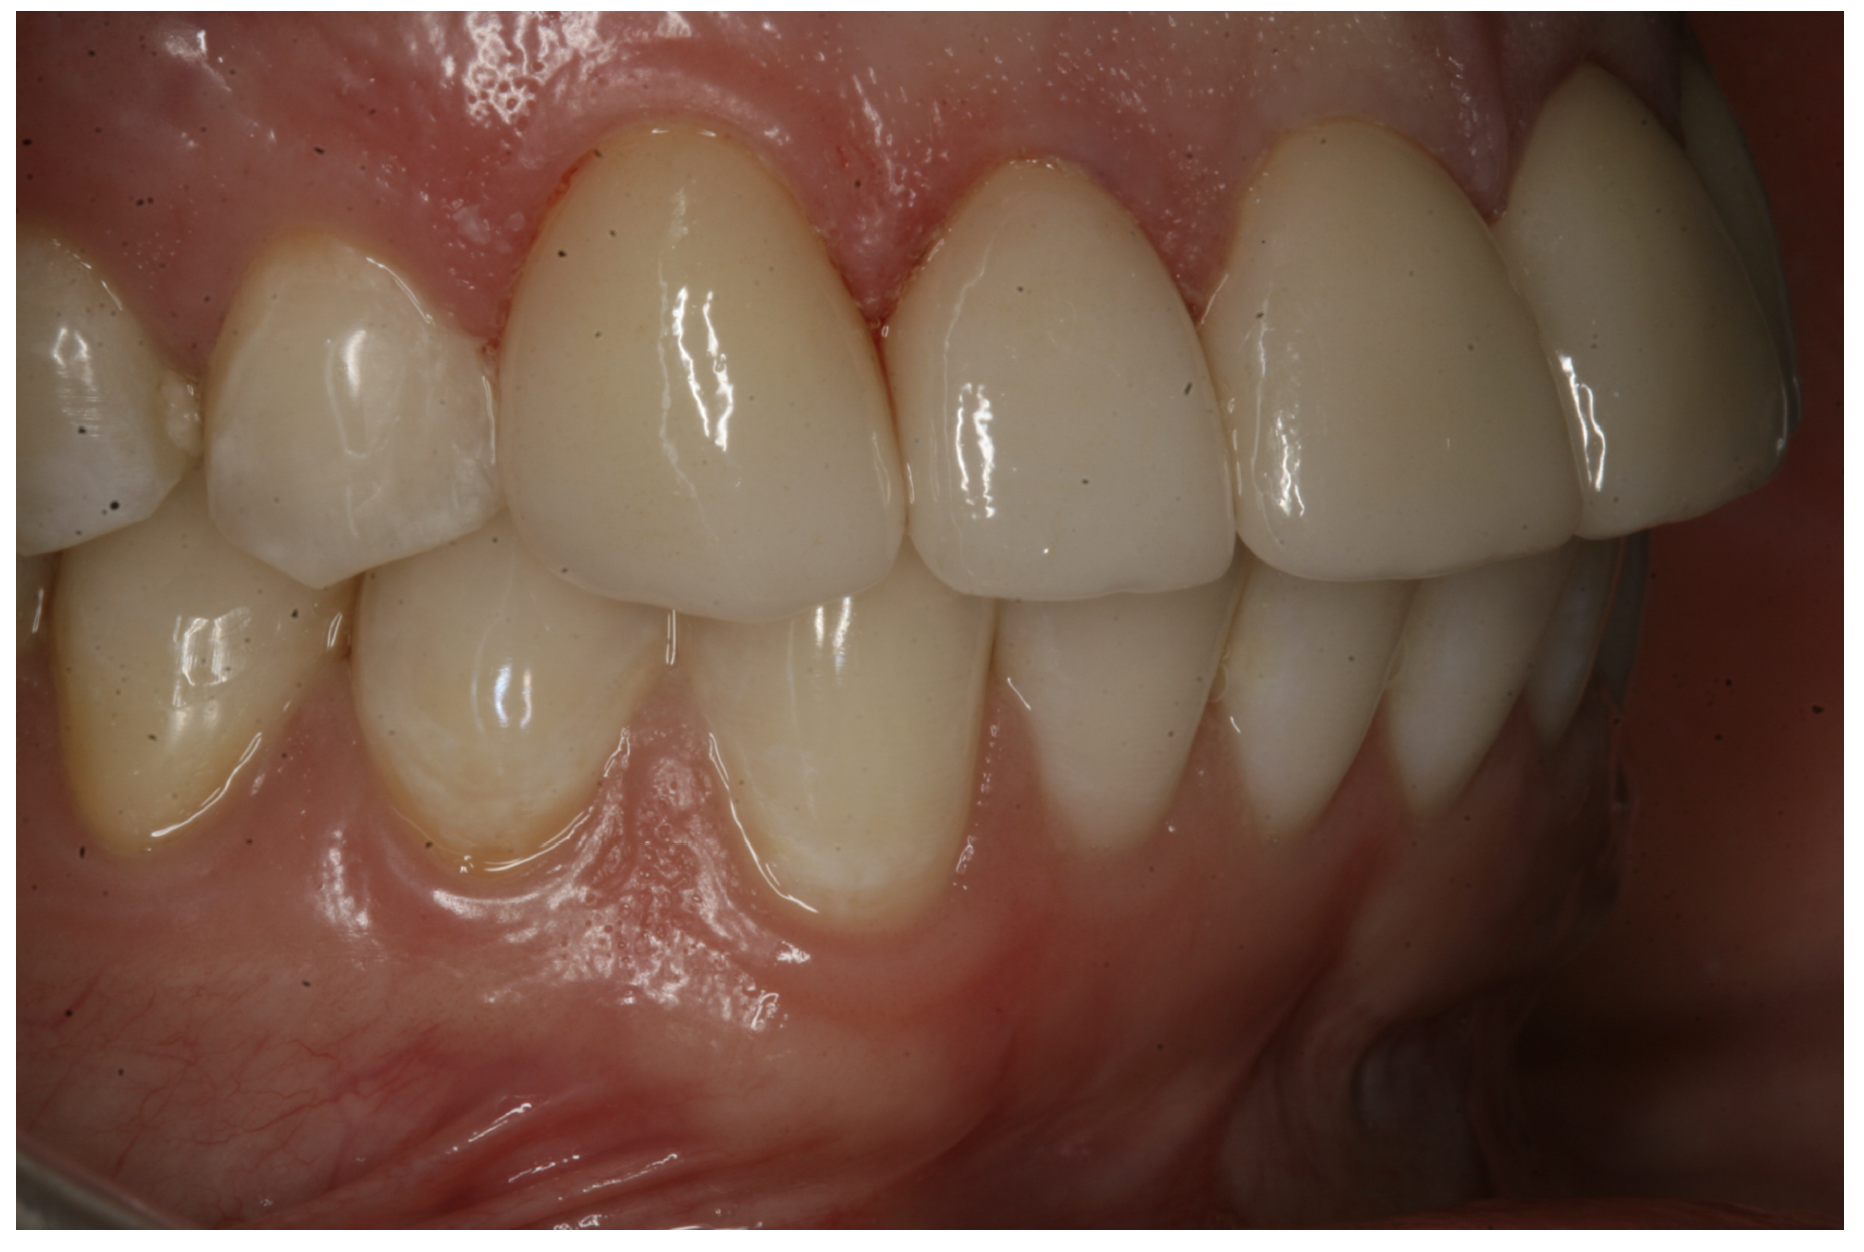

In the next case, the practitioner used a zirconia crown to replace an e.max crown on tooth No. 23 that had brown staining/discoloration. The practitioner used a universal to place the zirconia crown.  Excellent gum tissue health also was a result.

In another case, the patient presented with very thick, bulky, over-contoured veneers done on teeth Nos. 7 through 10 when she was a teenager. There also was some recession and staining at the margins (Figure 12). The clinician decided to restore teeth Nos. 6 through 11. A preparation design was required with provisionals removed. As tooth structure could not be regrown, the practitioner made the best of the situation. There was good gum health, which is important for isolation and marginal seal. The clinician cemented with a universal, doing six units at one time. Minimal cleanup was required. At a 1-month follow-up visit, although tissue still was settling in, the contours were natural. After a year (Figure 13), the gum filled in nicely and was in excellent health, and there was good color stability and seamless marginal integrity.